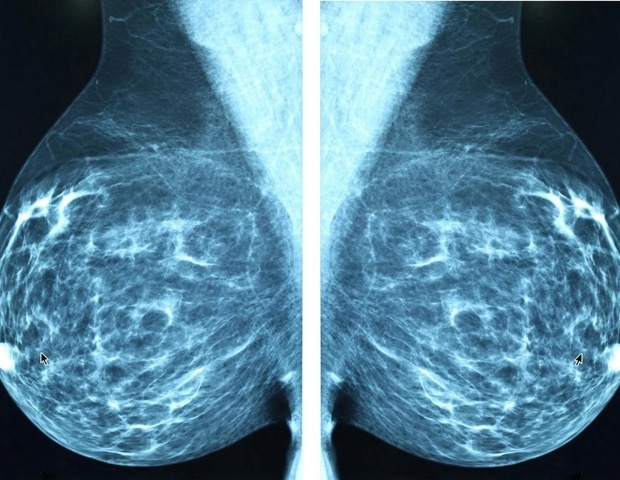

Пропуск биопсии сторожевого лимфатического узла (SLNB) у пациенток с клинически отрицательным по узлу, гормональным рецептором (HR)-положительным и HER2-отрицательным раком молочной железы на ранней стадии не поставил под угрозу региональный контроль или выживаемость после медианного пятилетнего наблюдения, согласно результатам клинического исследования BOOG 2013-08 фазы III, представленного на симпозиуме по раку молочной железы в Сан-Антонио (SABCS), состоявшемся в декабре 9–12, 2025 г.